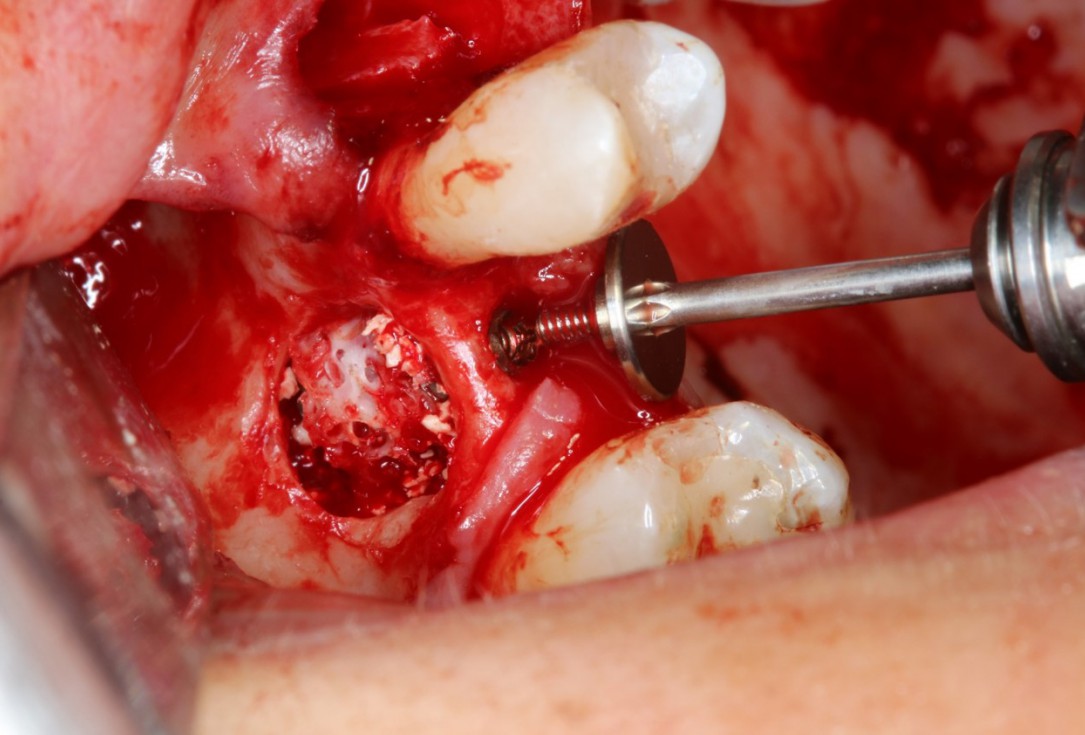

Periimplantitis treatment with maxgraft® bonering - Dr. B. Giesenhagen

Severe periimplantitis at tooth 15 with bone loss up to 1/3 of the implant